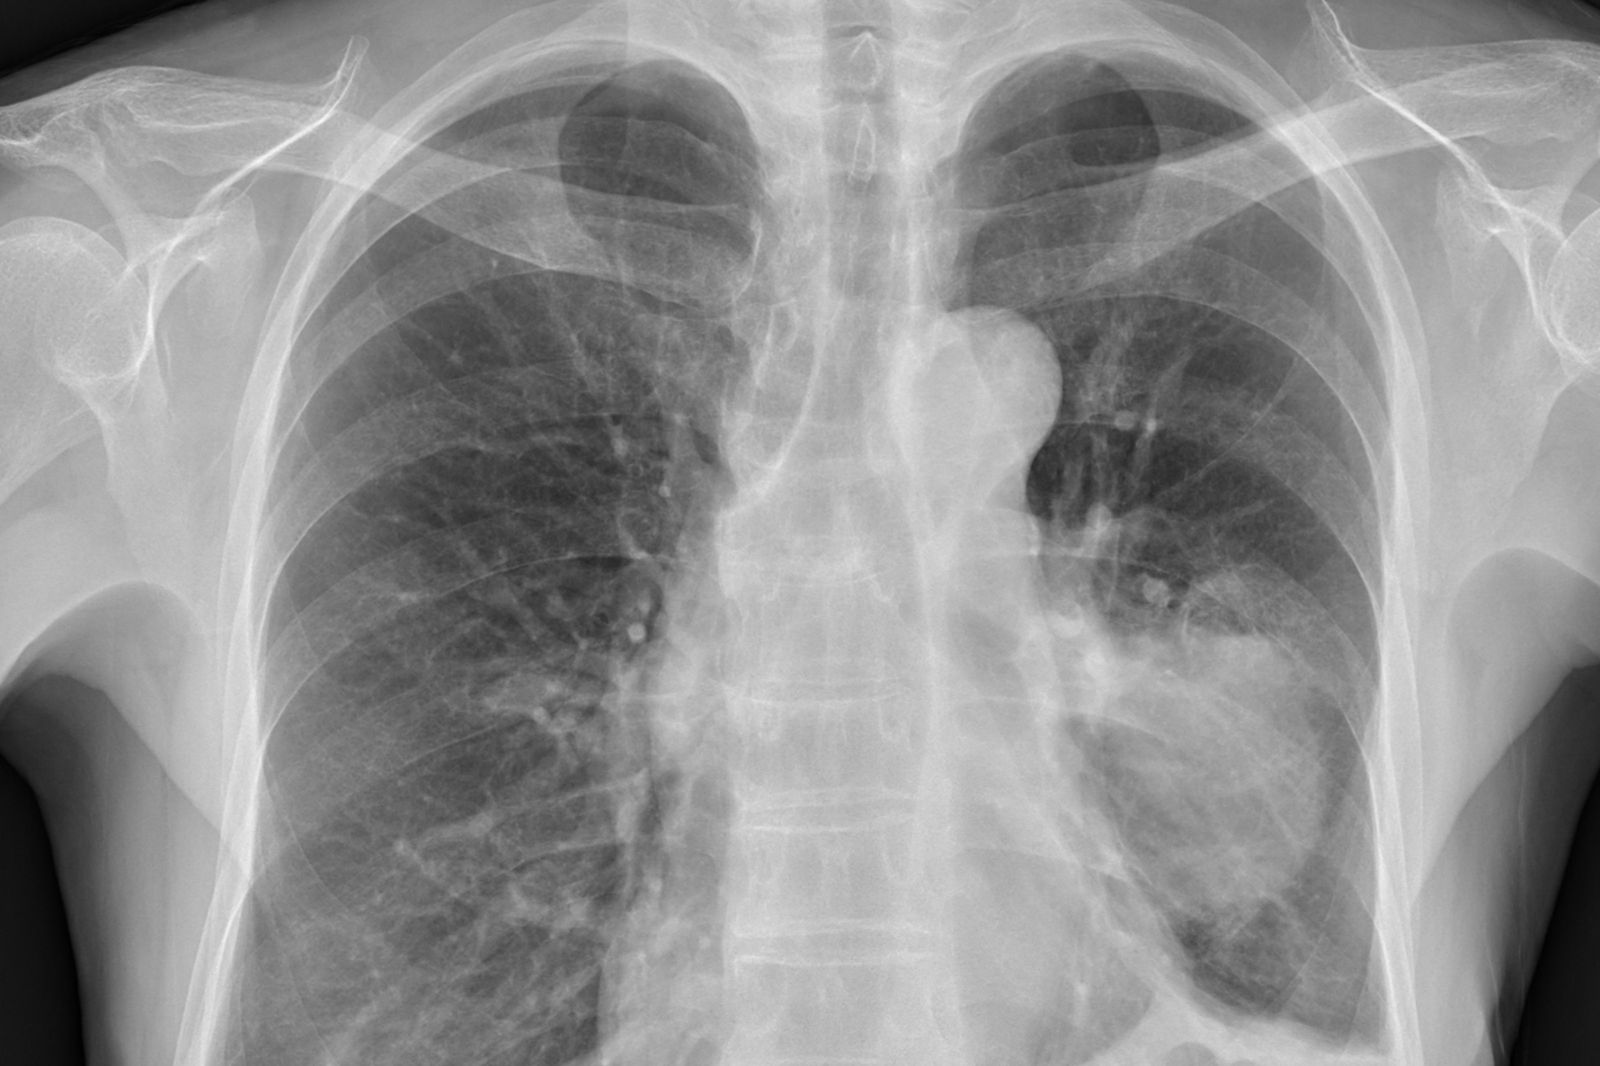

醫師蘇一峰在臉書粉專發布貼文,分享一名60歲婦女病例,這名婦女不喘也不咳嗽,平時不抽菸、不喝酒,但是最近體重逐漸變輕,兩三個月瘦了7、8公斤,一檢查照X光才發現,肺部的腫瘤已經長到7、8公分。蘇一峰指出,「台灣女性忍耐力很強,肺癌等到有症狀常常都是末期了,在台灣定期檢查肺癌真的非常需要,不能等到有症狀才來看醫師」。

肺癌的臨床症狀,視腫瘤長出的位置而異,周圍型的肺癌長在肺的周邊部位,早期幾乎沒有症狀,通常等到腫瘤大到一定程度,才出現胸痛、肋膜積水、呼吸困難等症狀,約有10%的肺癌患者甚至在確定診斷時並無臨床症狀。國泰綜合醫院表示,肺癌雖具有高死亡率與發生率逐年增加等特性,但由於與香菸之高相關性,要預防肺癌,戒除香菸仍是首要之務。由於肺癌早期都沒有症狀,所以對於高危險群之長期吸菸患者,應定期接受胸部X光、低劑量胸腔電腦斷層與痰液細胞學追蹤檢查,以期早期發現,以免延誤治療時機。